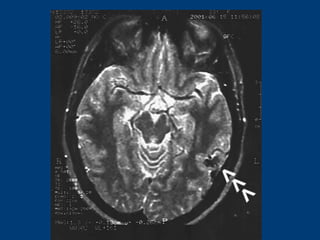

 S.Ç.: 32 yaşında kadın hastaS.Ç.: 32 yaşında kadın hasta

 Ani şiddetli başağrısı, B-KAni şiddetli başağrısı, B-K

CERRAHİCERRAHİ

 Sol frontoparyetal geniş kranyotomiSol frontoparyetal geniş kranyotomi

 AVM’nin total rezeksiyonuAVM’nin total rezeksiyonu